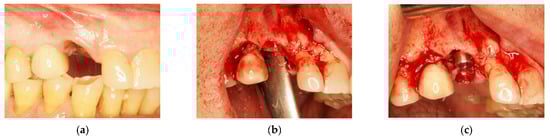

In order to rehabilitate the missing 1.3, an immediate post-extractive implant for tooth 1.3 was planned (Figure 6a–c). Blood clot was collected directly from patients (peripheral venous blood) and placed in a 5 mL vial. When the clot was thick enough due to coagulation, it was enriched with beta-tricalcium phosphate by rolling it on the surface of tricalcium granules: 1 g beta-tricalcium phosphate for every 5 mL of clot (Figure 7). Beta-tricalcium phosphate was chosen to stabilize the clot volume and for its capacity to be reabsorbed [61,62,63].

(a) Edentulous tooth site 13; (b) evaluation of the alveolus; (c) implant insertion.

After the implant insertion, the enriched clot was put in the alveolar gap and protected by a shaped intra-operatory titanium foil, fixed with screws on both buccal and palatal walls. It sutured, leaving the foil exposed (Figure 8a,b).

(a) Protection of the alveolus with titanium foil; (b) titanium foil; (c) follow-up at 6 months.

Six months after surgery, the high quality and stability of soft tissues was observed (Figure 8c).

The titanium barrier was removed and the growth of new bone tissue, even if not completely mature, was observed (Figure 9a). After a further 6 months, we noted how pre-existing keratinized gingiva of keratinized mucosa indicated by the arrow in Figure 9a, contributed to the formation of the adherent gingiva band as shown in Figure 9b.

(a) Flap of keratinized mucosa indicated by the arrow; (b) finalization with a prosthetic crown.